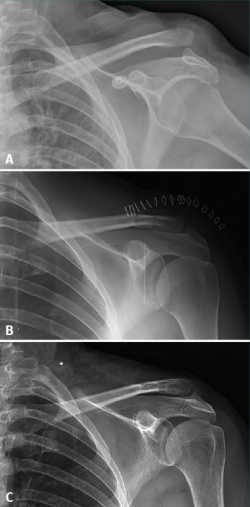

Figure 2. An 18-year-old male presenting type V acromioclavicular dislocation initially subjected to conservative management. One year after the injury he presented persistent symptoms and absolute limitation for sports activities (A). Surgery was performed with good reduction of the deformity (B), and four years after the operation the functional outcome was excellent (C), with minimum degenerative changes in the acromioclavicular joint and some widening of the clavicular tunnels.